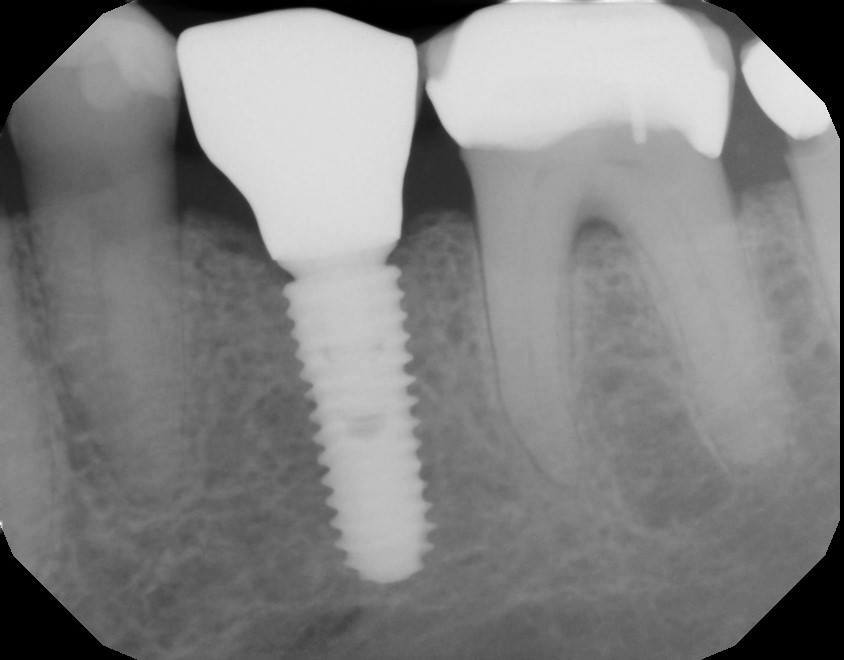

Fig 14. A periapical radiograph of the custom healing abutment on the implant demonstrated the development of a natural emergence profile for a mandibular molar to replicate the missing natural tooth.

Figure 14

A 4.8 mm x 10 mm implant (Straumann® Bone Level Tapered [BLT], Straumann) had been placed at the mandibular first molar site and was ready for restoration. A custom healing abutment was fabricated and inserted at the time of surgical implant placement and soft tissue was sutured around the abutment using 4/0 Glycolon sutures (Osteogenics Biomedical, osteogenics.com) (Figure 13). A periapical x-ray was taken at the time of placement of the custom healing abutment to confirm full seating (Figure 14).

After a 6- to 8-week healing period, the custom healing abutment was removed to allow for a digital scan of the area as an alternative to conventional impression-taking (Figure 15 and Figure 16). An intraoral scan body was used to capture the soft-tissue profile and implant positioning with an intraoral scanner (CEREC® Omnicam, Dentsply Sirona) (Figure 17). Final seating of the restoration was performed with radiographic confirmation (Figure 18). The implant crown demonstrated a natural emergence profile to replace the mandibular first molar with optimized tissue fill in the interproximal regions (Figure 19).